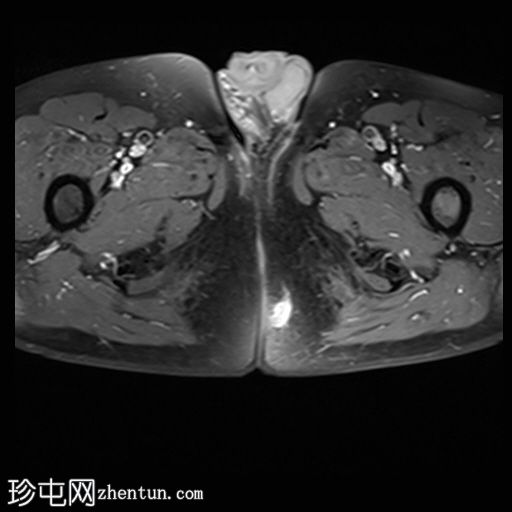

轴向位

T1

位于5点钟和6点钟位置之间,在STIR和T2加权图像上呈高信号。

瘘管起源于括约肌间平面附近,穿过肛门内外括约肌,并延伸至左侧坐骨肛门窝。瘘管内充满液体信号,周围有轻微水肿。肛提肌上方未观察到颅骨延伸。

根据圣詹姆斯大学医院的磁共振分类系统,该病例被归类为III级左侧肛周经括约肌瘘,左侧坐骨肛门窝可见炎症改变。